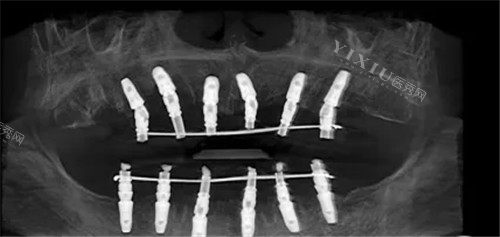

1. 智能化种植中心:即刻种与高龄种技术

爱顿口腔的智能化种植技术是其核心优势之一。"即刻种"技术实现了,采用小创口手术方式,术后舒适度高且愈合快速。对于老年患者,其"高龄种"技术通过精细植入方案,减少植体数量,无需骨移植,手术过程快速舒适,种植体稳固耐用。这些技术特别适合单颗、多颗牙缺失、半全口缺失、牙槽骨流失以及活动义齿不适的患者。

2. 全口/半口种植解决方案

针对全口或半口缺牙患者,爱顿口腔提供较高的效率的种植方案,具有创口小、改善期短的特点。种植后的牙齿无异物感,既美观又坚固,能够改善接近天然牙的咀嚼功能。对于牙槽骨萎缩重度或伴有种植禁忌症的患者,医院也能提供个性化的解决方案。